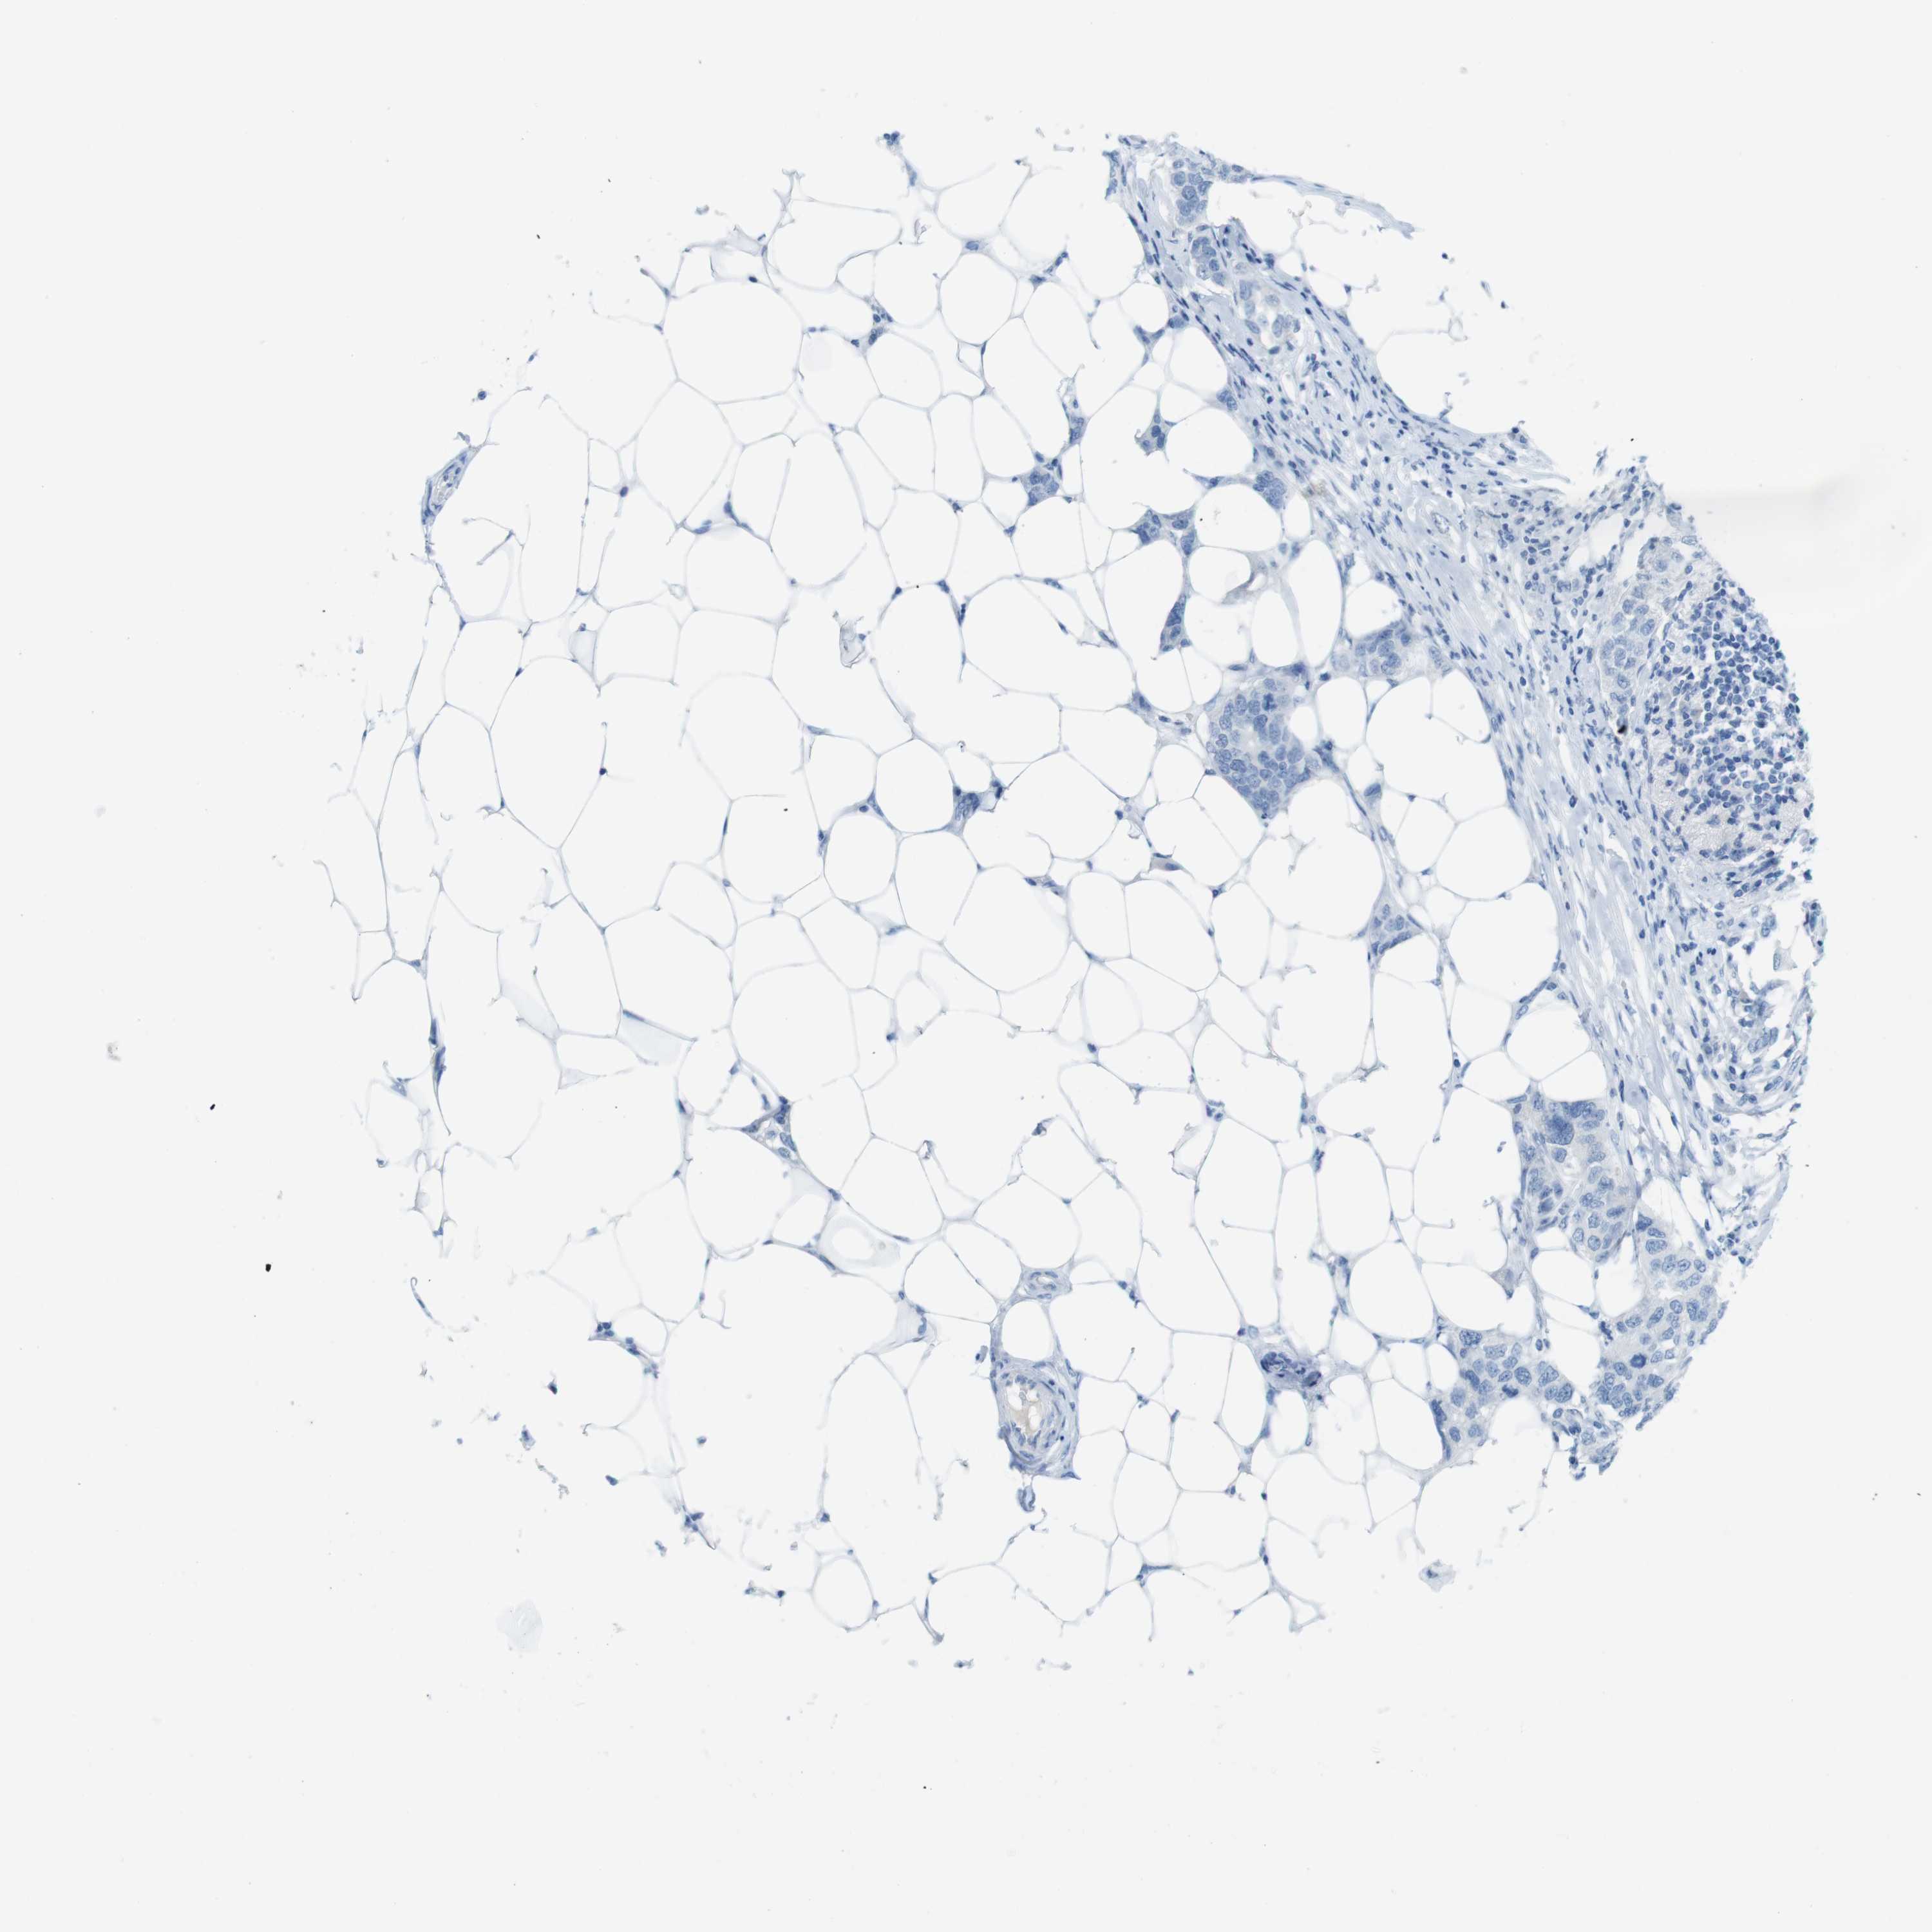

Breast cancer

Human cancer